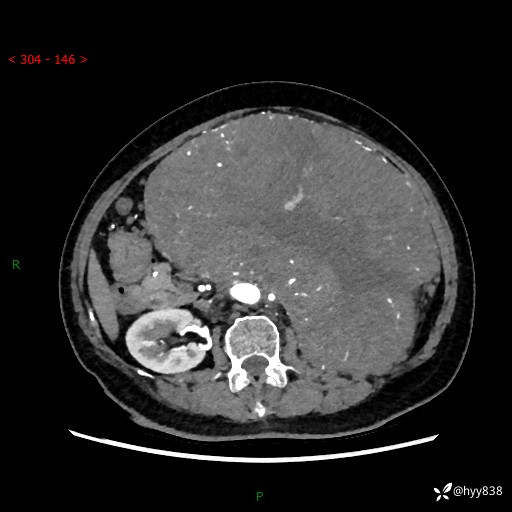

据说只有腹膜后,才能见到如此巨大的肿块---(有结果)

主诉:发现腹膜后占位1周

简要病史:患者1周前因头晕在当地第二人民医院检查发现左侧腹膜后区巨大富血供占位性病变,患者自诉腹部稍硬,无其他不适,无血尿,无腰痛等不适,患者为求进一步治疗来我院,门诊以“腹膜后占位性病变”收入我科。 起病以来,患者精神、饮食、睡眠可,大便正常,小便如上述,体力体重无明显改变。

临床诊断:腹膜后占位

腹部CT增强(动脉期+静脉期 ) ---平扫外院